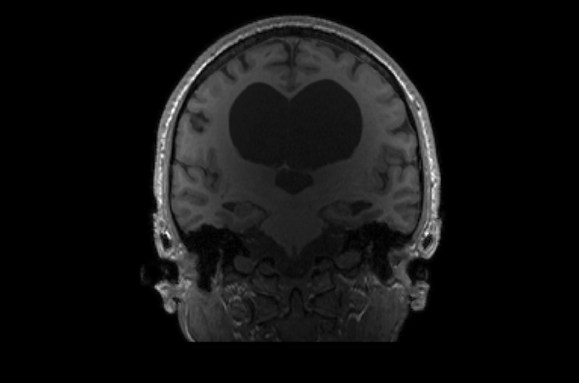

Elyse G. found out she lacked most of her left temporal lobe when she was 25 years old. The brain region is typically crucial for speech and language — but until her brain was scanned (three views shown), no one knew Elyse was missing hers.

Looking at her brain scans is a different story. It’s as if someone has knocked over a bottle of ink. The darkness pools inside her skull near her left ear, a puddle of fuliginous black. Inside the splotch, there’s no white matter or gray matter, no blood vessels or tissue at all.

Elyse says you don’t have to be a neurosurgeon to spot what’s different about her brain: “There’s a big honking piece missing!”

As of May 30, the Interesting Brains Project had scanned the brains of 30 people. Some have holes in their frontal or temporal lobes; others are missing parts of their cerebellum, a brain structure involved in balance and movement. Still other participants have brain matter that’s squished up against the sides of their skull; scans show voids that appear to have ballooned from the brain’s center.